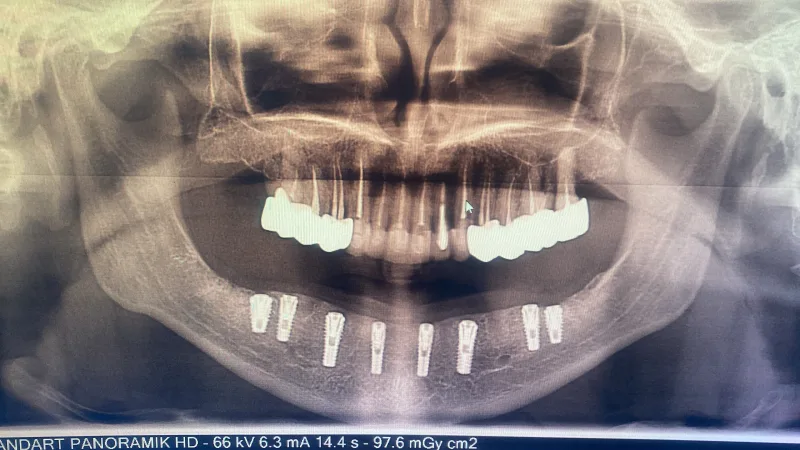

✅ Proteesit ja hampaiden implantointi